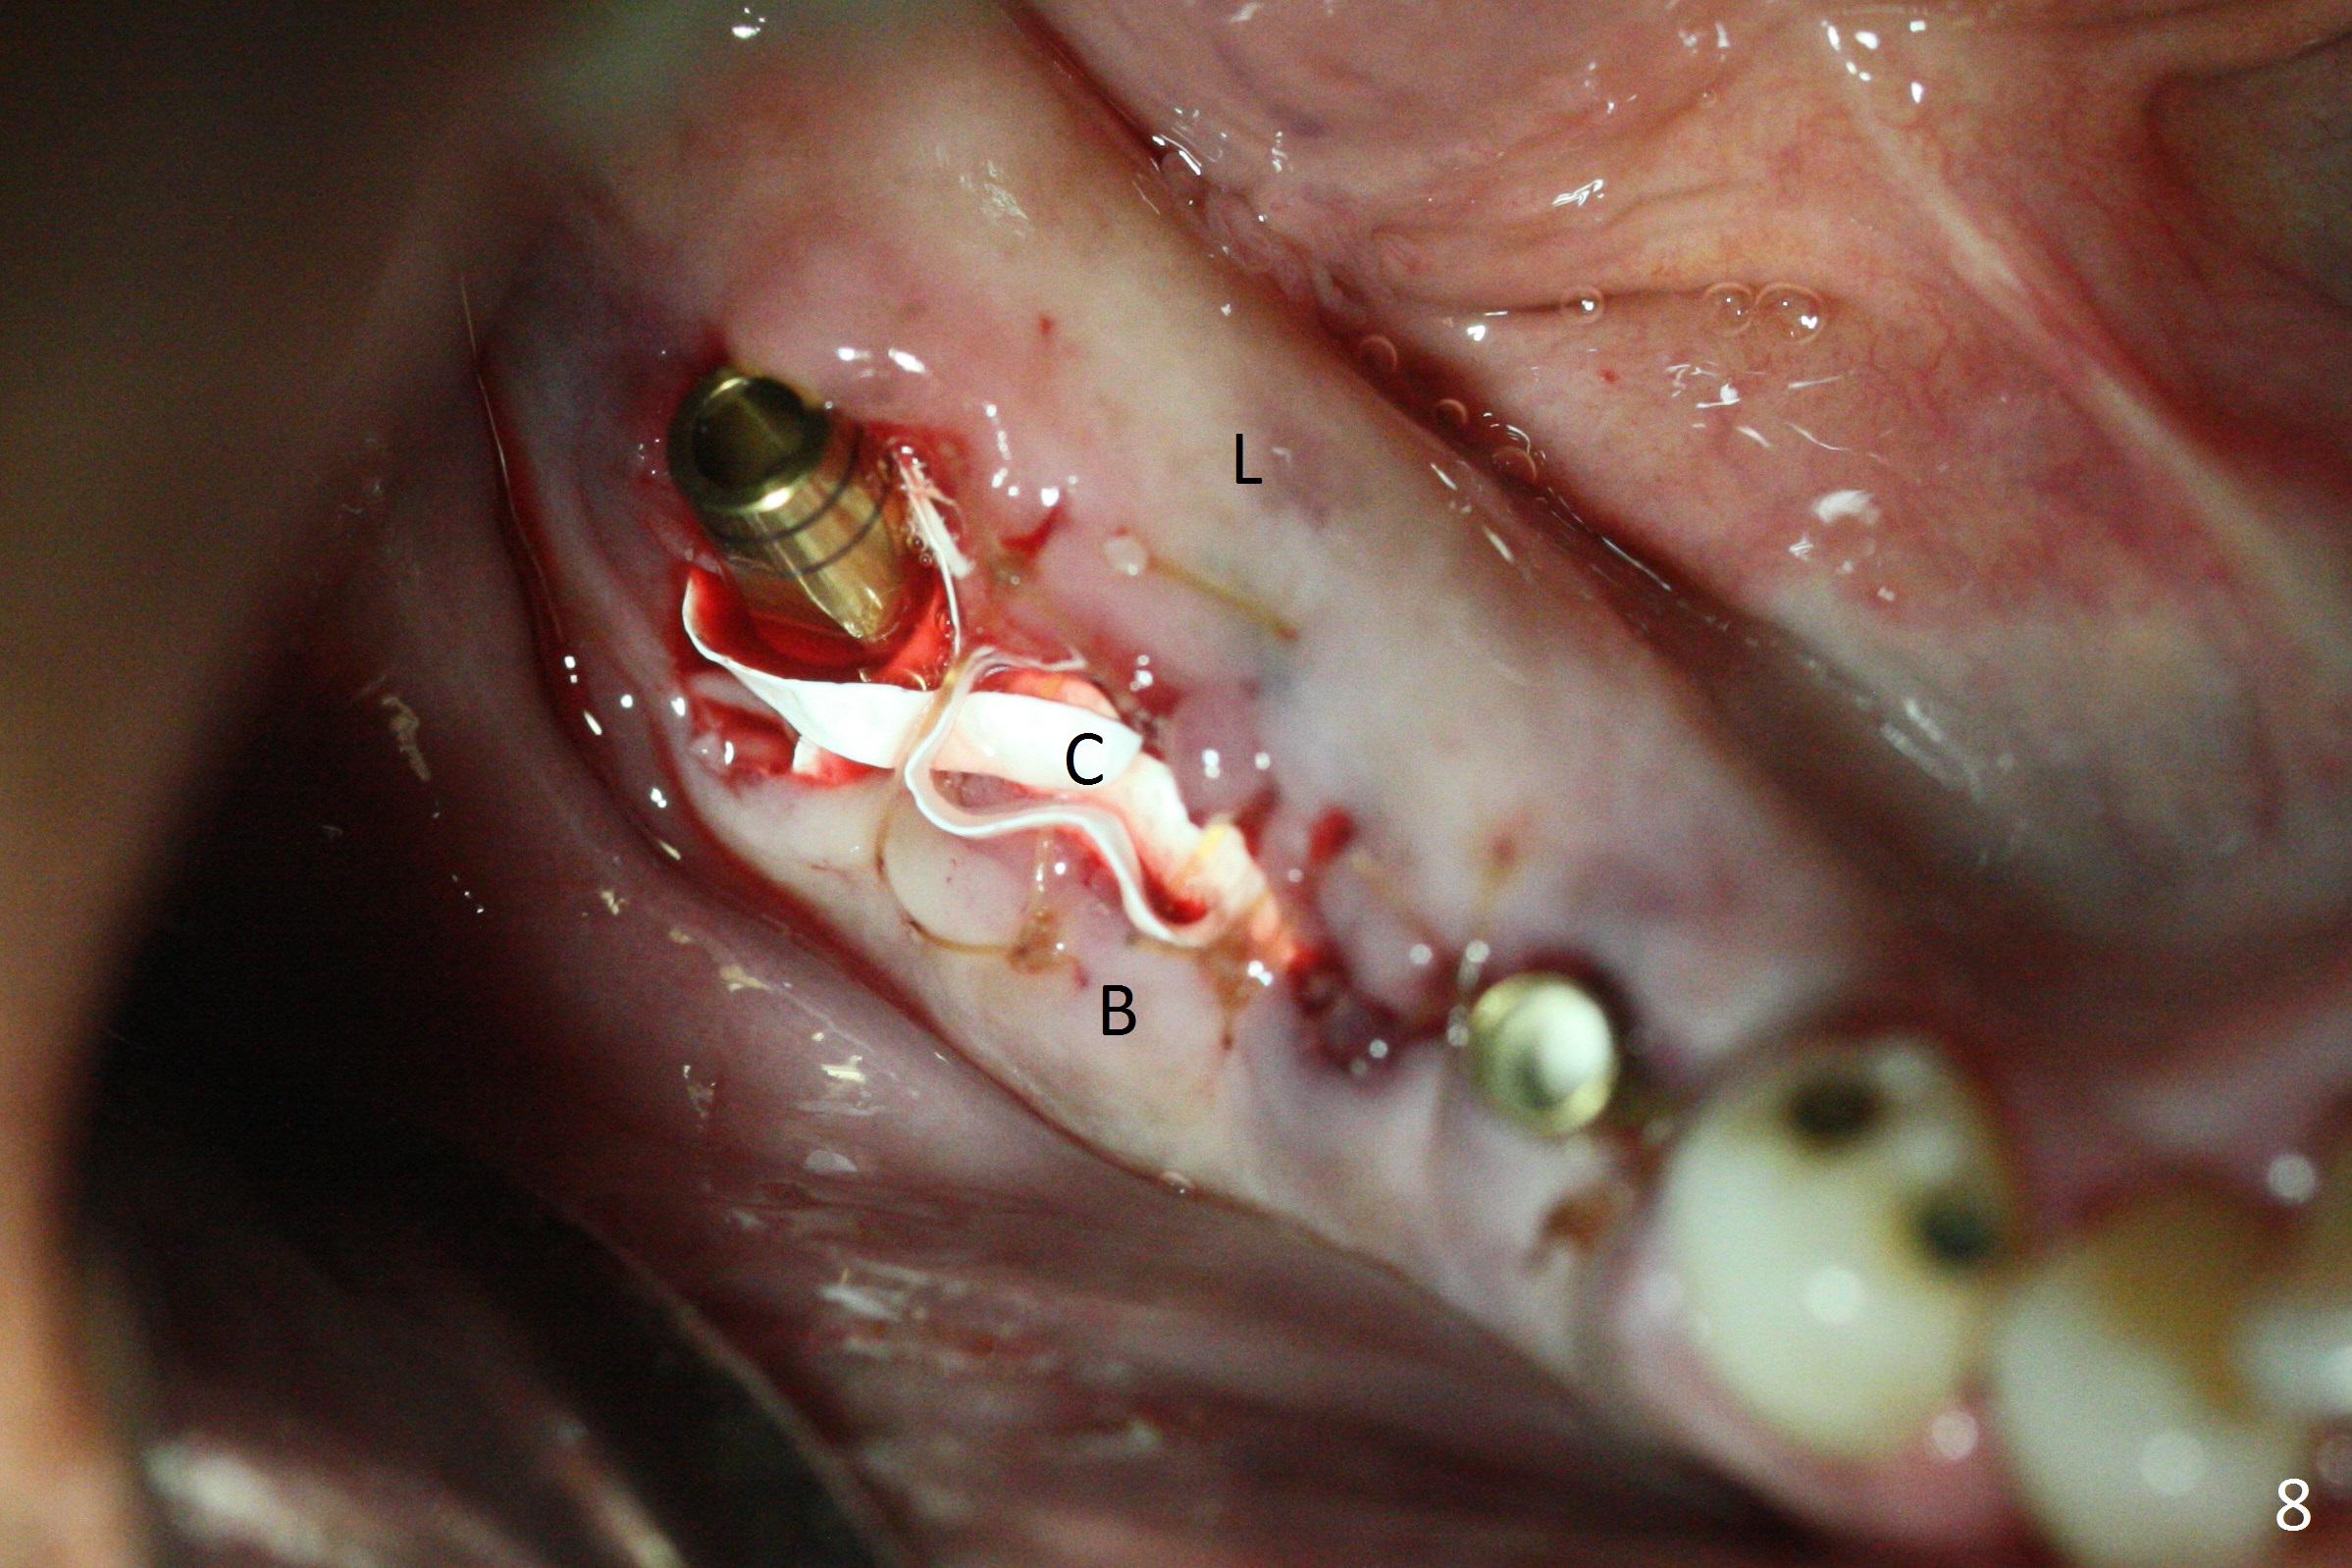

At #31, the implant has to be placed low because of low buccal bone (Fig.8 B (vs. much higher lingual (L) one) in spite of 2 mm implant being coronal to the distal bone (Fig.3 ^). The margin of the abutment with 6 mm cuff appears apical to the distal crest (Fig.3 *). Bone graft is placed around the exposed implant threads (Fig.6 *) after placement of Osteogen plug between the implants (P). After placing PRF membrane (Fig.7 M) and plug (P) over the bone graft, Cytoplast (Fig.6,8 C: non-resorbable membrane) is used to assist wound closure. Finally periodontal dressing is applied for further wound protection (Fig.9).